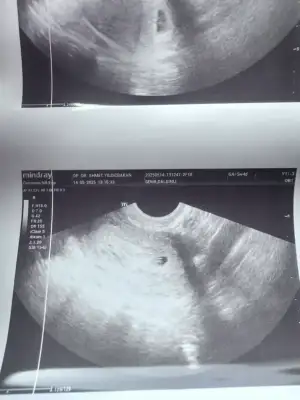

Kızlar keseme bakar mısınız normal mi 5+2 bugün doktor dedi bebek var içinde 10 gün sonra kalp atışına çağirdi

• IMG_3583.webp

IMG_3583.webp

37,9 KB · Görüntüleme: 24